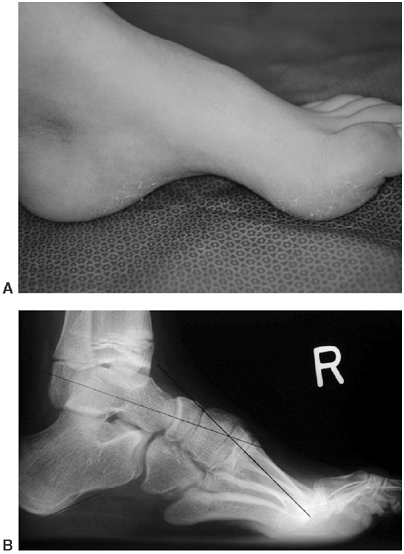

![]() |

Figure 16.10 A–D:

Newborn infant with open myelomeningocele and severe kyphosis. Closure and reduction of the kyphosis was performed simultaneously with resection of vertebral bodies and tension band fixation. B: At 6-year follow-up, the child has only mild residual kyphosis that is not progressive and does not require any further treatment. (Courtesy of Charles T. Price, MD) |